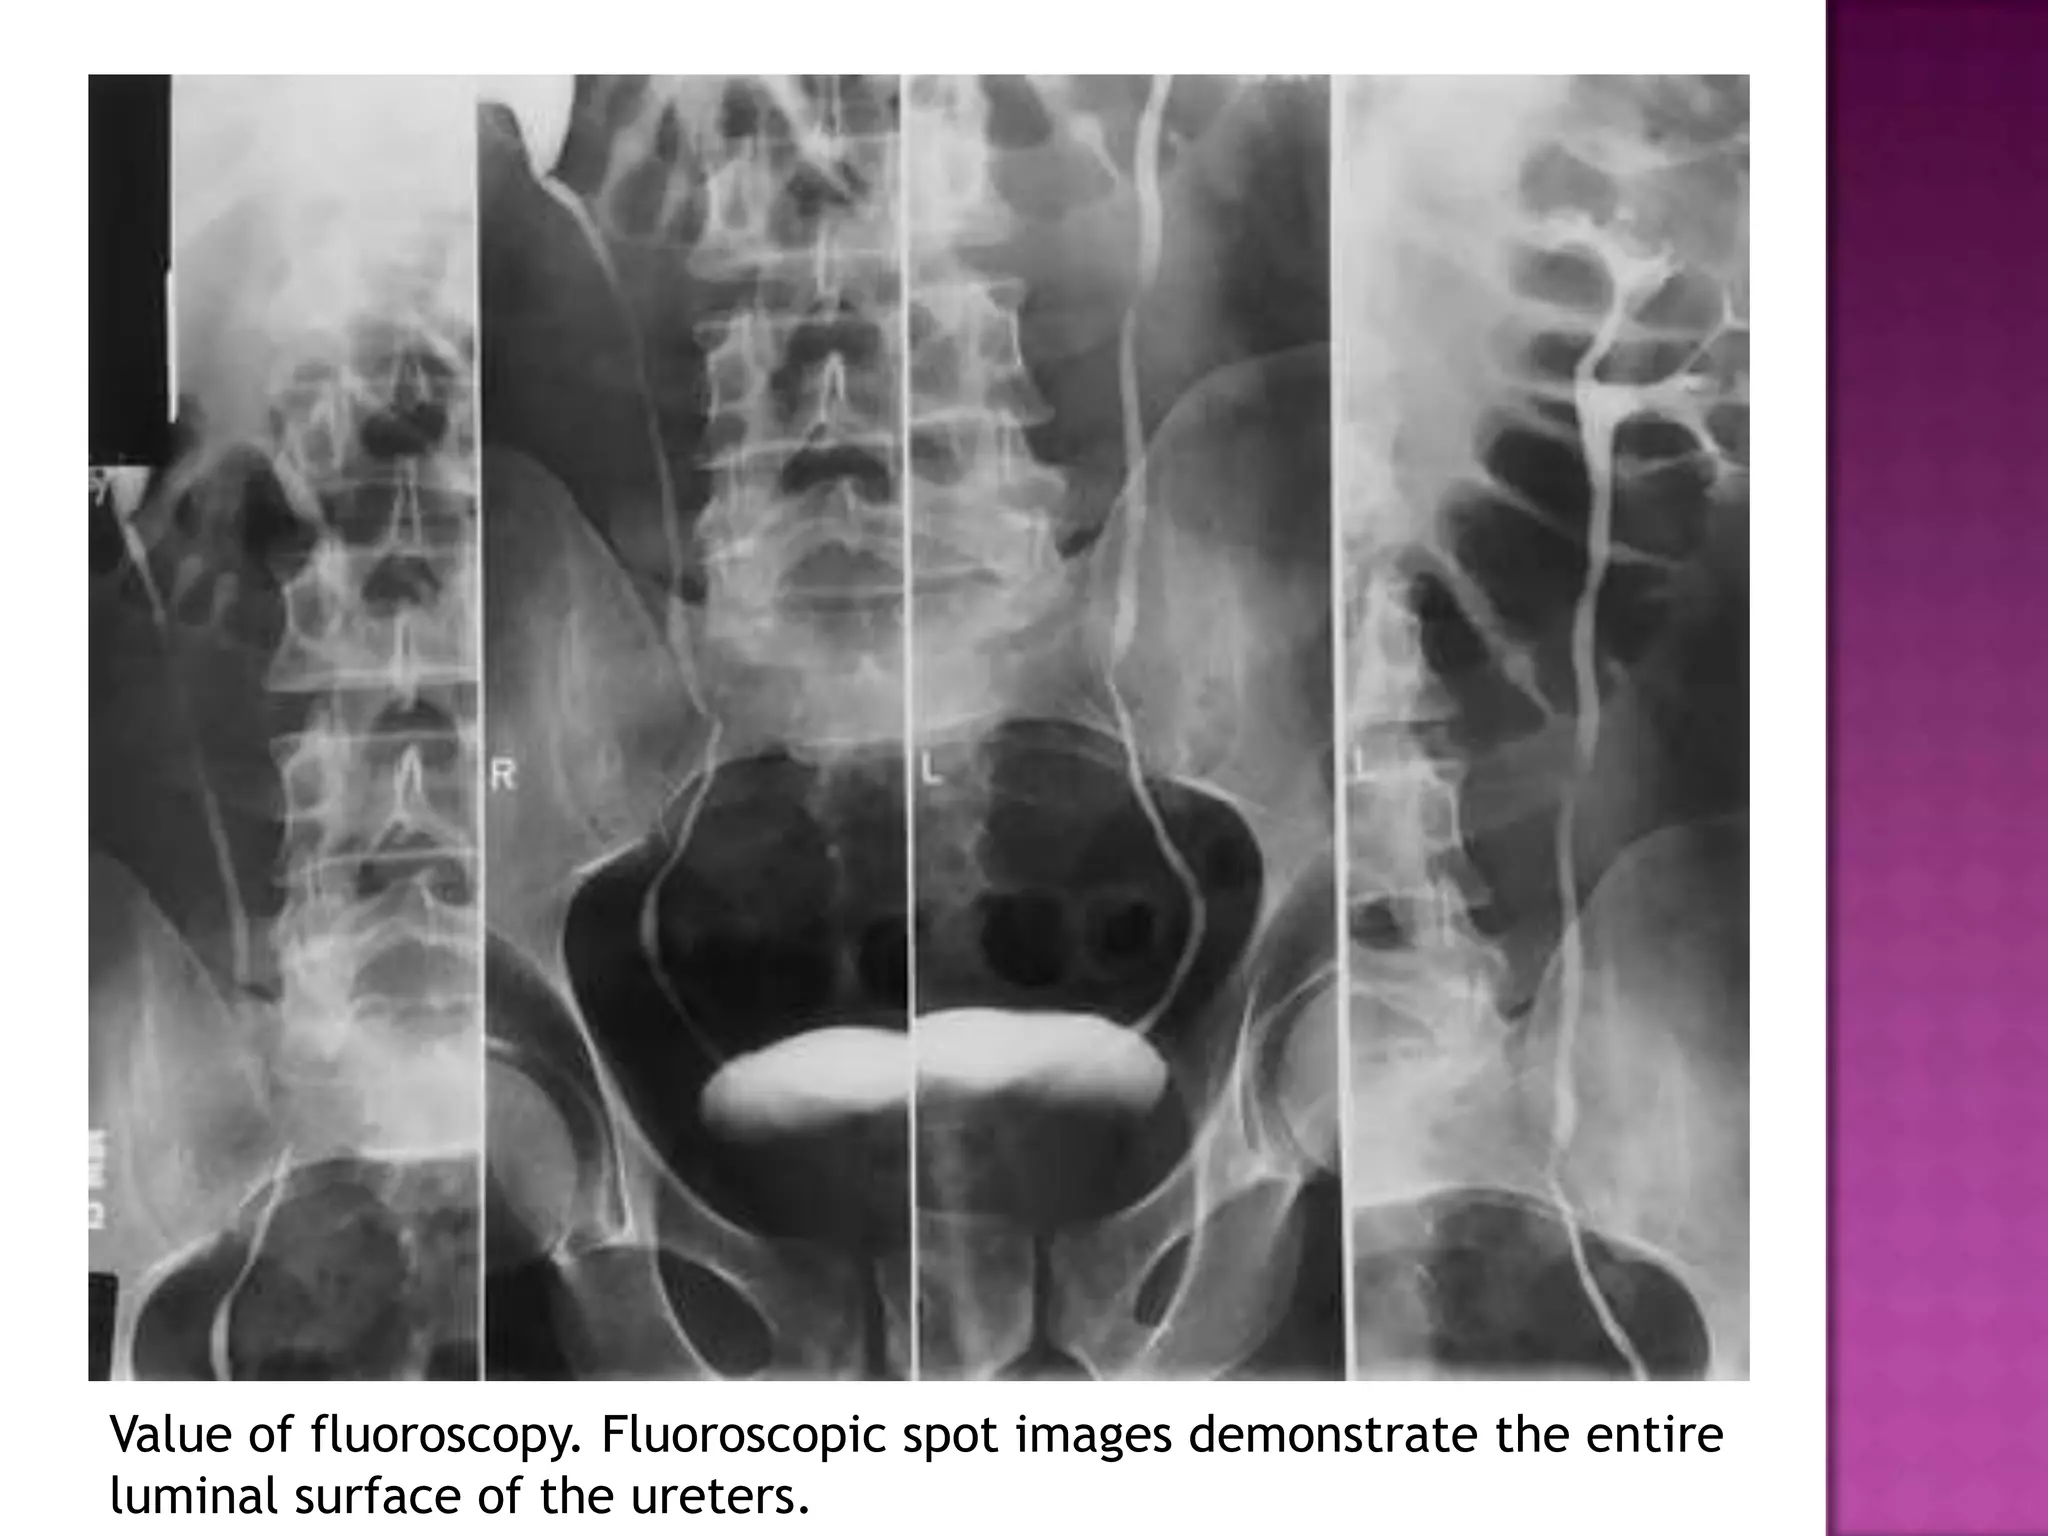

Value of fluoroscopy. Fluoroscopic spot images demonstrate the entire

luminal surface of the ureters.

Value of fluoroscopy.Fluoroscopic spot images demonstrate the entire luminal surface of the ureters.